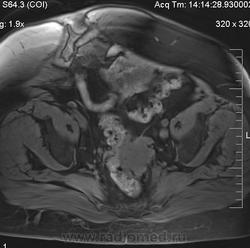

очень характерная картина для метастаза рака яичника, к сожалению.

Не могу достоверно определить локализацию метастаза брюшной полости, вероятно в лимф. узел с инвазией оободочной кишки. Рецидив С-r левого яичника думаю, что с инфильтацией левой стенки прямой кишки и культи влагалища, вторичная лимфаденопатия л/у малого таза. каликопиелоуретероэктазия (инвазия нижних отделов левого мочеточника?) Холедох широковат, но желтухи по внешнему виду нет.

Прорастание левого мочеточника рецидивной опухолью есть 100%, метастаз в большой сальник характерен для рака яичников, как и сигнальные характеристики его. Культя в данном случае шейки матки.